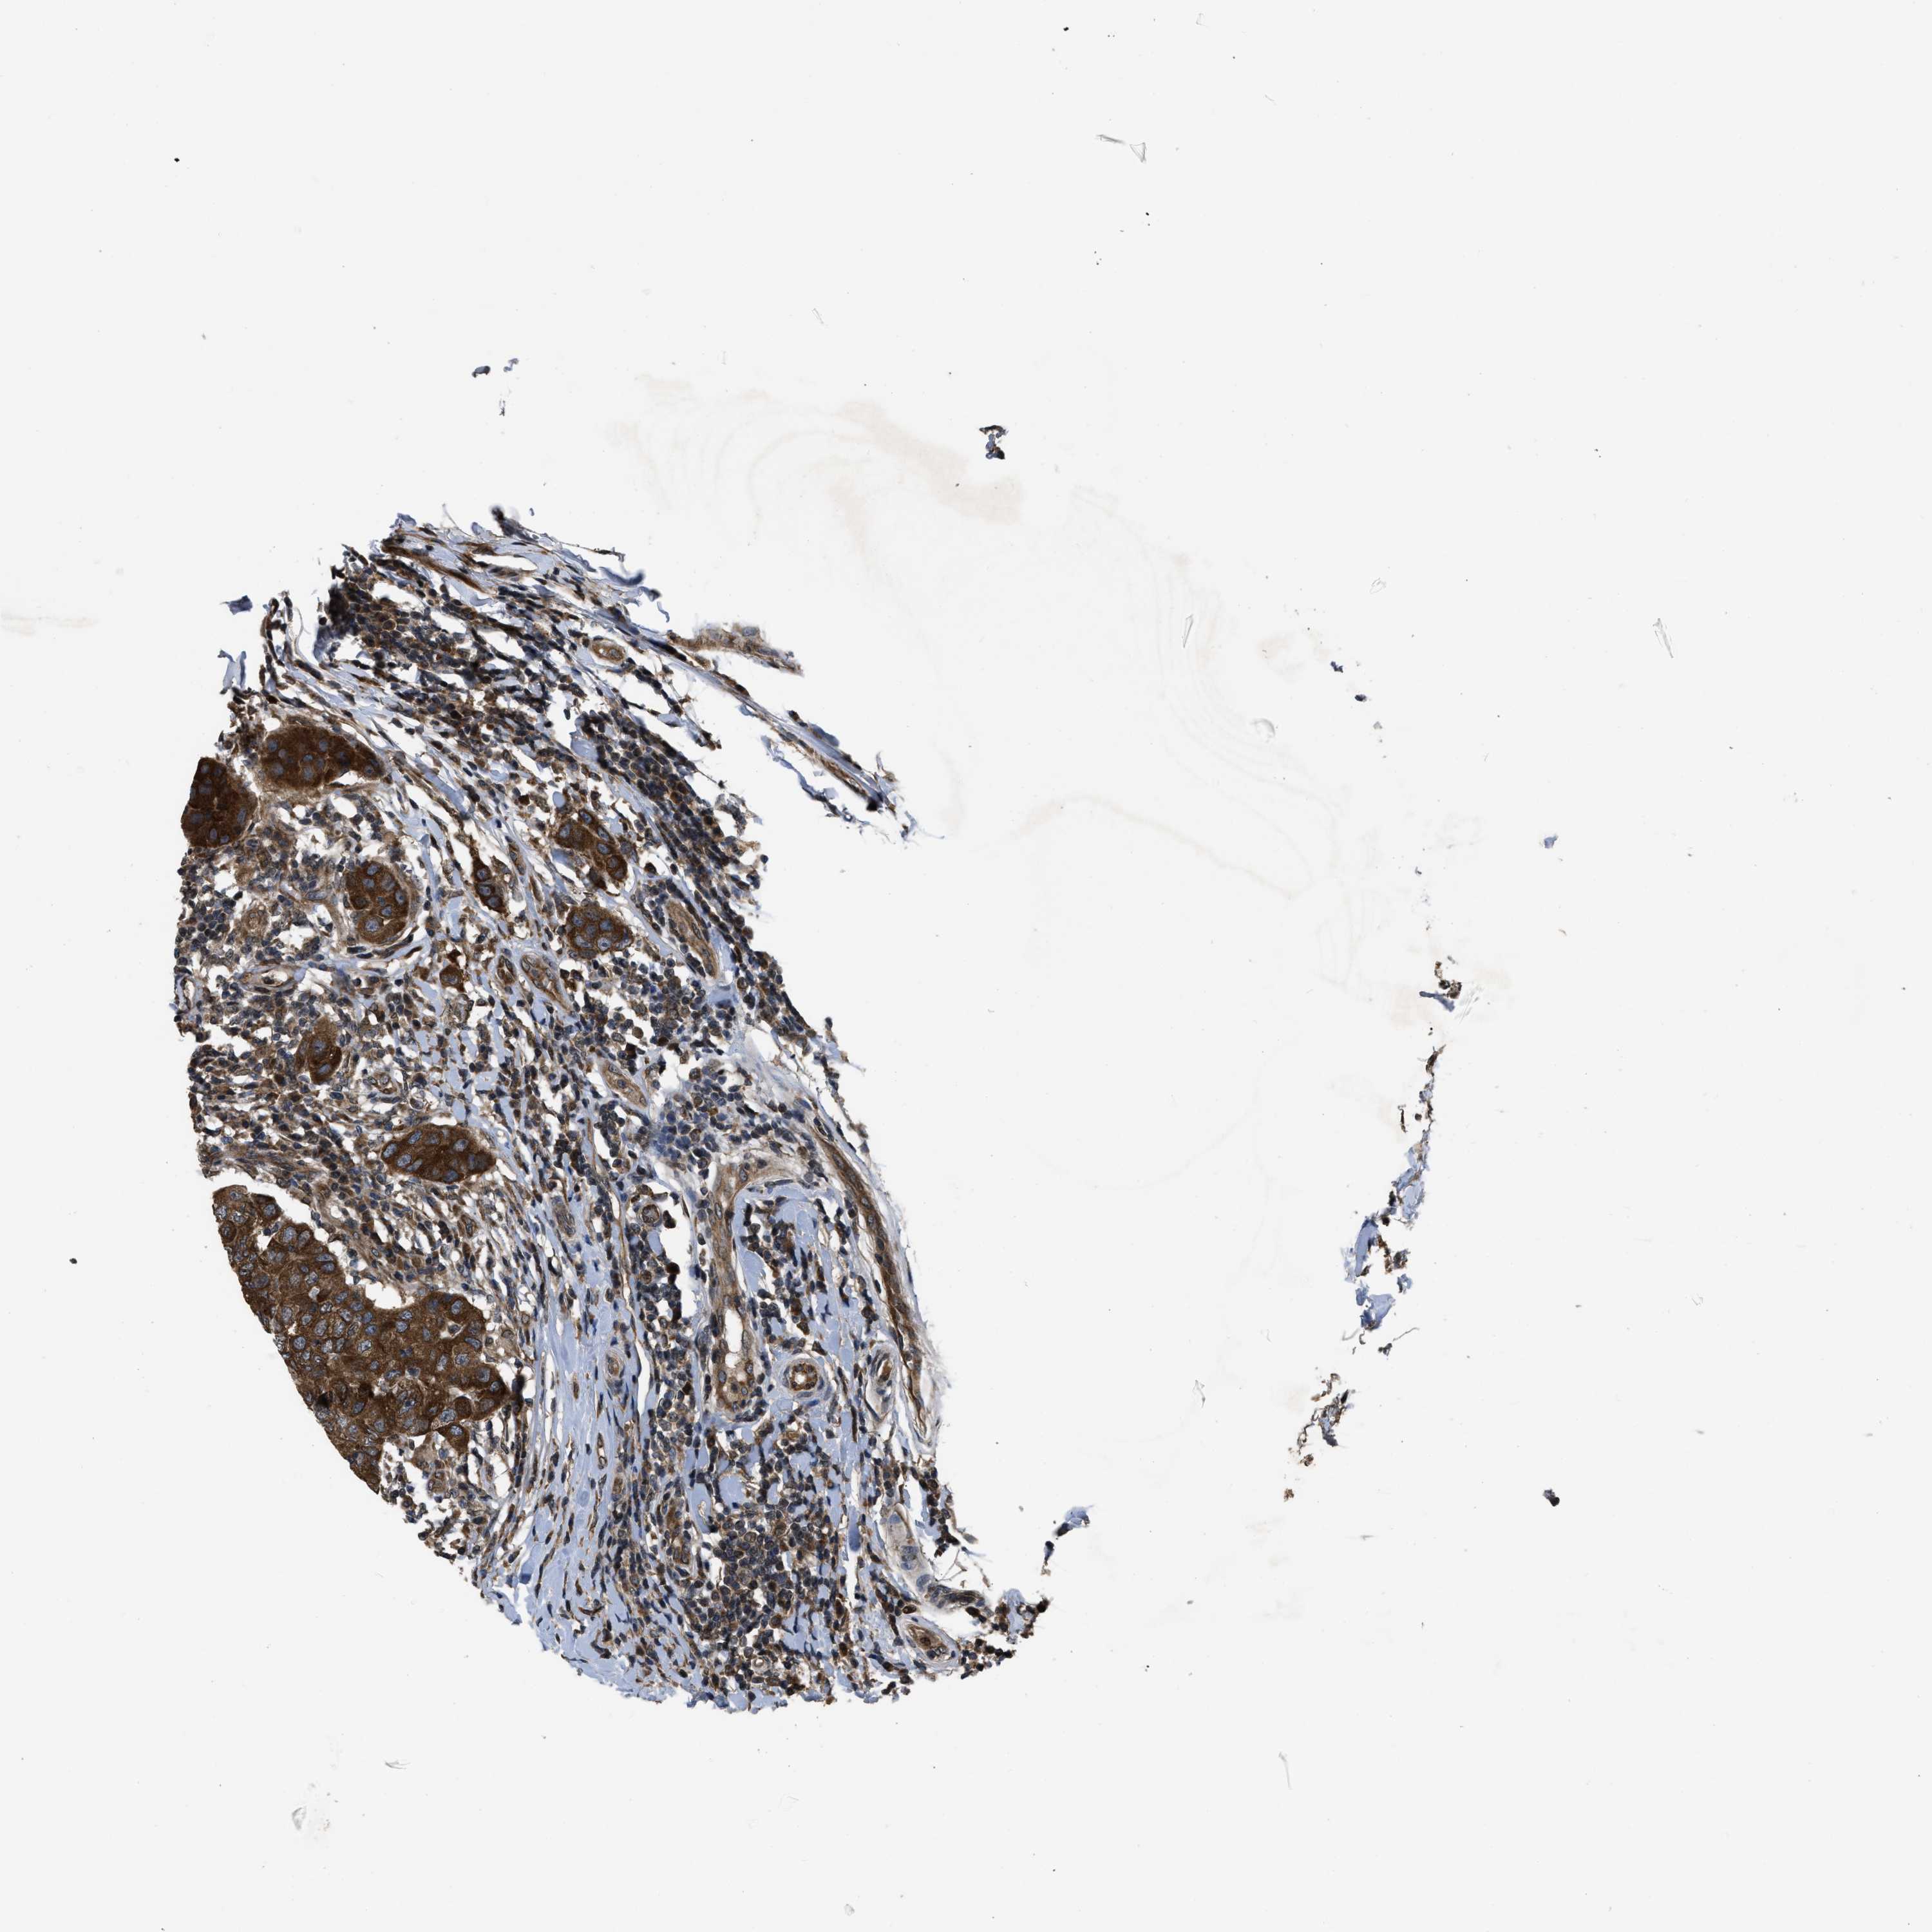

CANCER BREAST CANCER Show tissue menu

BRCA TCGA BRCA VALIDATION PROTEIN EXPRESSION

Breast cancer

Human cancer